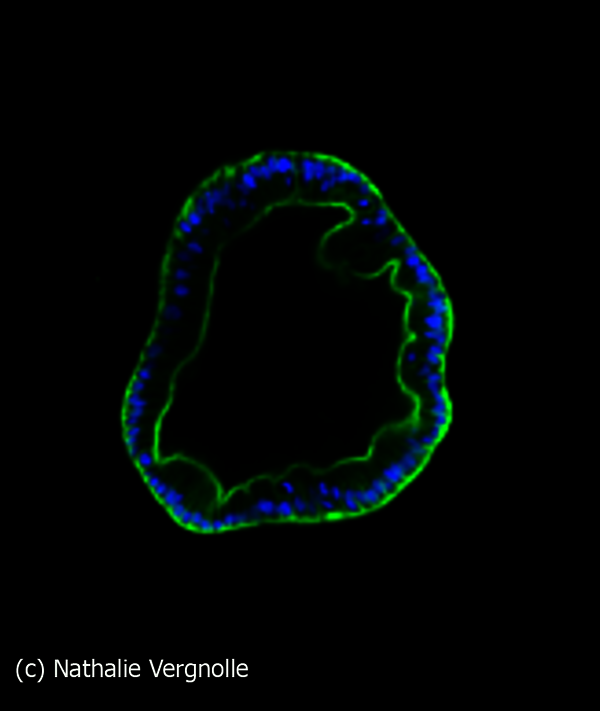

Ce prix récompense son travail de Thèse réalisé dans l'équipe "RCPG, douleur et inflammation".